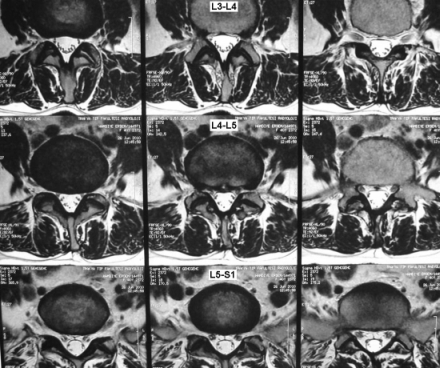

Lomber MRG Aksiyal Kesit - Anüler Yırtık

Resim 2: Hastanın T2 ağırlıklı aksiyal MRG kesitlerinde belirgin bir disk herniyasyonu veya foraminal darlık bulunmadığı, L4-L5 seviyesinde anulusta yüksek sinyal intensitesi olduğu görülmektedir.